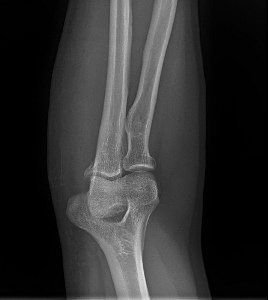

Estimation of Body Size From Individual Bones

Calculate the approximate height of the person if a humerus bone was found in a Caucasian male femur of 50.6cm